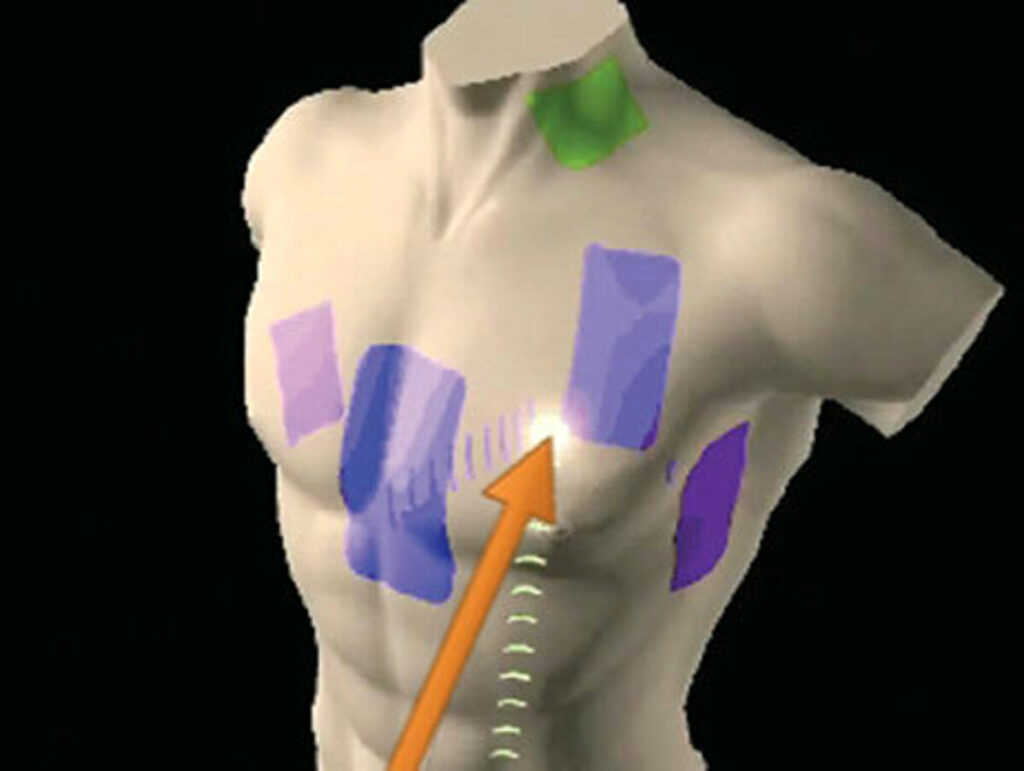

All’Ospedale Civico di Palermo arriva una tecnologia rivoluzionaria, grazie alla visualizzazione 3D della struttura cardiaca. Il nuovo metodo, chiamato EnSite X, permette di realizzare un modello anatomico tridimensionale dell’organo, consentendone la visualizzazione in tempo reale ed una nuova modalità di lettura del segnale cardiaco.

Tramite l’innovativa tecnologia dell’EnSite X, è possibile contribuire alla realizzazione di importanti passi avanti nella diagnosi e nel trattamento delle aritmie cardiache complesse. L’elettrofisiologo, infatti, è così in grado di conoscere la velocità di conduzione all’interno della camera cardiaca del paziente e sapere con esattezza la direzione di attivazione elettrica.

«Grazie a questa tecnologia, di cui siamo precursori in Italia, oggi possiamo visualizzare una mappa tridimensionale ad alta risoluzione del cuore e avere informazioni in tempo reale sulle aree responsabili dell’aritmia, migliorando la qualità e la durata delle procedure di ablazione con un tasso di successo più elevato a beneficio dei pazienti», aggiunge Sergio Conti che, insieme ai dottori Gregory Dendramis, Umberto Giordano e Vito Pinto, fa parte della straordinaria équipe del laboratorio di Elettrofisiologia della Cardiologia del Civico.